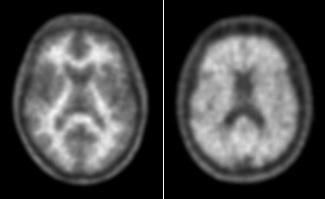

- Henryk Barthel, M.D., Ph.D., University of Leipzig, Germany, presented “Early ß-amyloid PET images are a valuable surrogate biomarker of neuronal injury in dementia patients,” which showed that a single tracer injection may provide information on both neuronal integrity (as FDG) and beta-amyloid deposition.

Neuraceq was approved in the United States and European Union earlier this year. It is indicated for positron emission tomography (PET) imaging of the brain to estimate beta-amyloid neuritic plaque density in adult patients with cognitive impairment who are being evaluated for Alzheimer’s disease and other causes of cognitive decline.